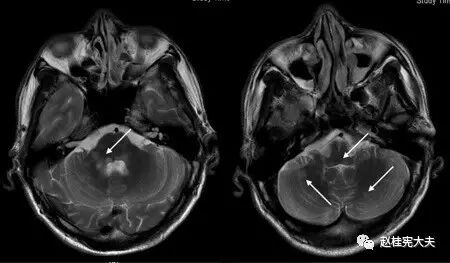

图2. 示双侧桥臂、延髓、小脑多发圆形或卵圆形病灶,T2高信号。

图10. (上图)T1、(下图)T2 FLAIR像示:病灶累及脑桥、延髓、双侧小脑。

多发性斑块在MR上表现为多灶性T1WI等或低信号,T2加权图像(FLAIR序列上尤为明显)上特征性不同程度的高信号,可反映脑灰、白质炎症病变;部分病灶在增强图像上表现为局灶性钆对比增强性信号改变,反映局部急性血脑屏障破坏和活动性炎症反应;较大的活动性斑块在DWI上亦可显示弥散受限。

视神经受侵犯时,呈现T2高信号并可伴视神经增粗,与单纯MS相比,NMO视神经病变范围更广泛,可延伸到视神经后部甚至视交叉,且病变通常呈对称性分布[3];MS脊髓受累者,病灶多>3 mm且<2个椎体节段,横断面上<1/2脊髓面积且水肿轻,而NMOSD脊髓病变可扩展到3个以上脊髓水平,但部分亚洲MS患者的脊髓病灶长度可≥2个椎体节段,AQP4抗体检测有助于鉴别。